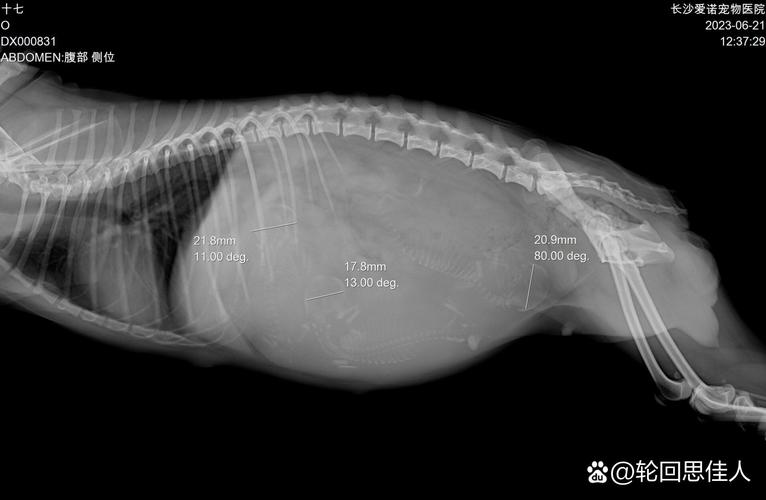

一般来说,狗狗在6个月到1岁之间进入青春期,这时候身体已经发育成熟,可以开始繁殖。不过,比较好等到狗狗1岁到2岁之间再进行繁殖,因为此时狗狗身体完全成熟,更容易承受分娩的压力,也有更高的生产优势。如果狗主人想让狗狗有准确的生产时间,可以请医生通过B超检查,预测狗狗的分娩日期。

狗狗通常在6个月到1岁之间进入青春期,此时身体发育成熟,可以开始繁殖。 建议在狗狗1岁到2岁之间进行繁殖,因为此时狗狗身体完全成熟,更容易承受分娩压力,生产更具优势。 若想准确预测狗狗的生产时间,可通过B超检查来预测分娩日期,以便做好分娩前后的准备工作,确保母狗及其宝宝的安全。